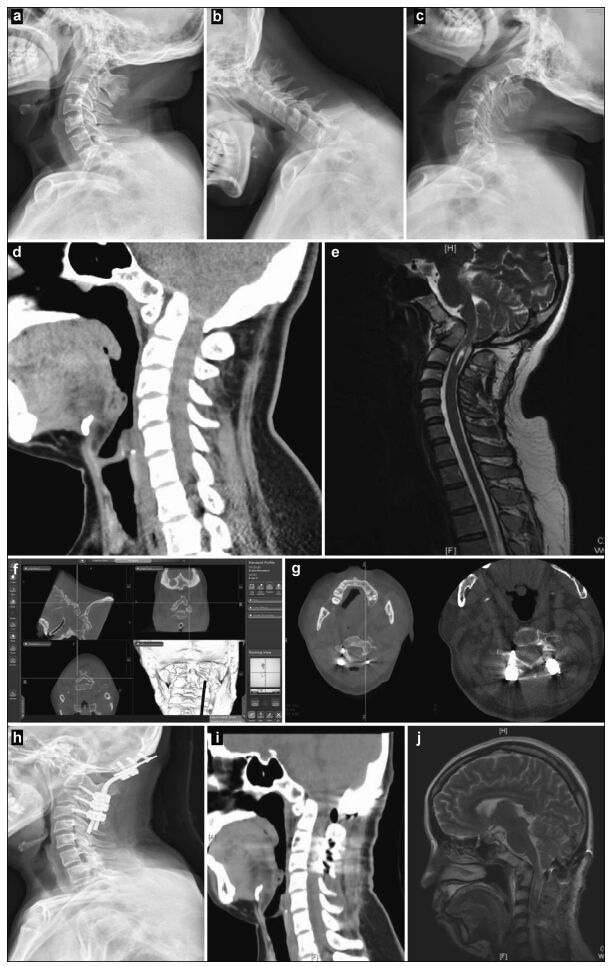

| Figure 1 Preoperative, intraoperative, and postoperative images of patients with atlantoaxial dislocation and occipitocervical fusion. Preoperative cervical radiography in the side (a), anteflexion (b), and supine (c) positions reveals odontoid instability and a backward and upward shift. Preoperative computed tomography (CT) (d) and magnetic resonance imaging (MRI) (e) show that the backward and upward dislocation of the C2 odontoid impacts the brain stem. The foramen magnum is narrow, and the cervical cord void is visible. (f) Implantation direction and C2 angle. Pars screws are planed under intraoperative navigation. (g) O-arm three-dimensional scan, after screw implantation, shows that the Pars screw to the right of C2 penetrates the bone cortex and is near the vertebral artery. Lateral radiography (h), sagittal CT (i), and a T2 sagittal scan (j), 1 week after the operation, show firm screw fixation in a good position and inferoanterior displacement of the odontoid to the C1 level, essentially achieving normal anatomical reduction. Brain stem compression is released, and the posterior cranial fossa is fully decompressed. |